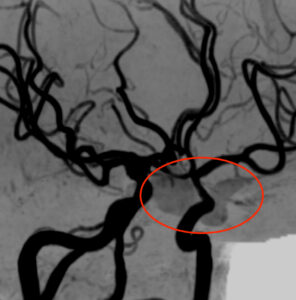

MRA検査(脳の血管を撮像したもの)を見ると、

下垂体に相当する部分に、血管外部に血流を示す信号を認め、下垂体卒中(下垂体腫瘍からの出血)と診断しました。